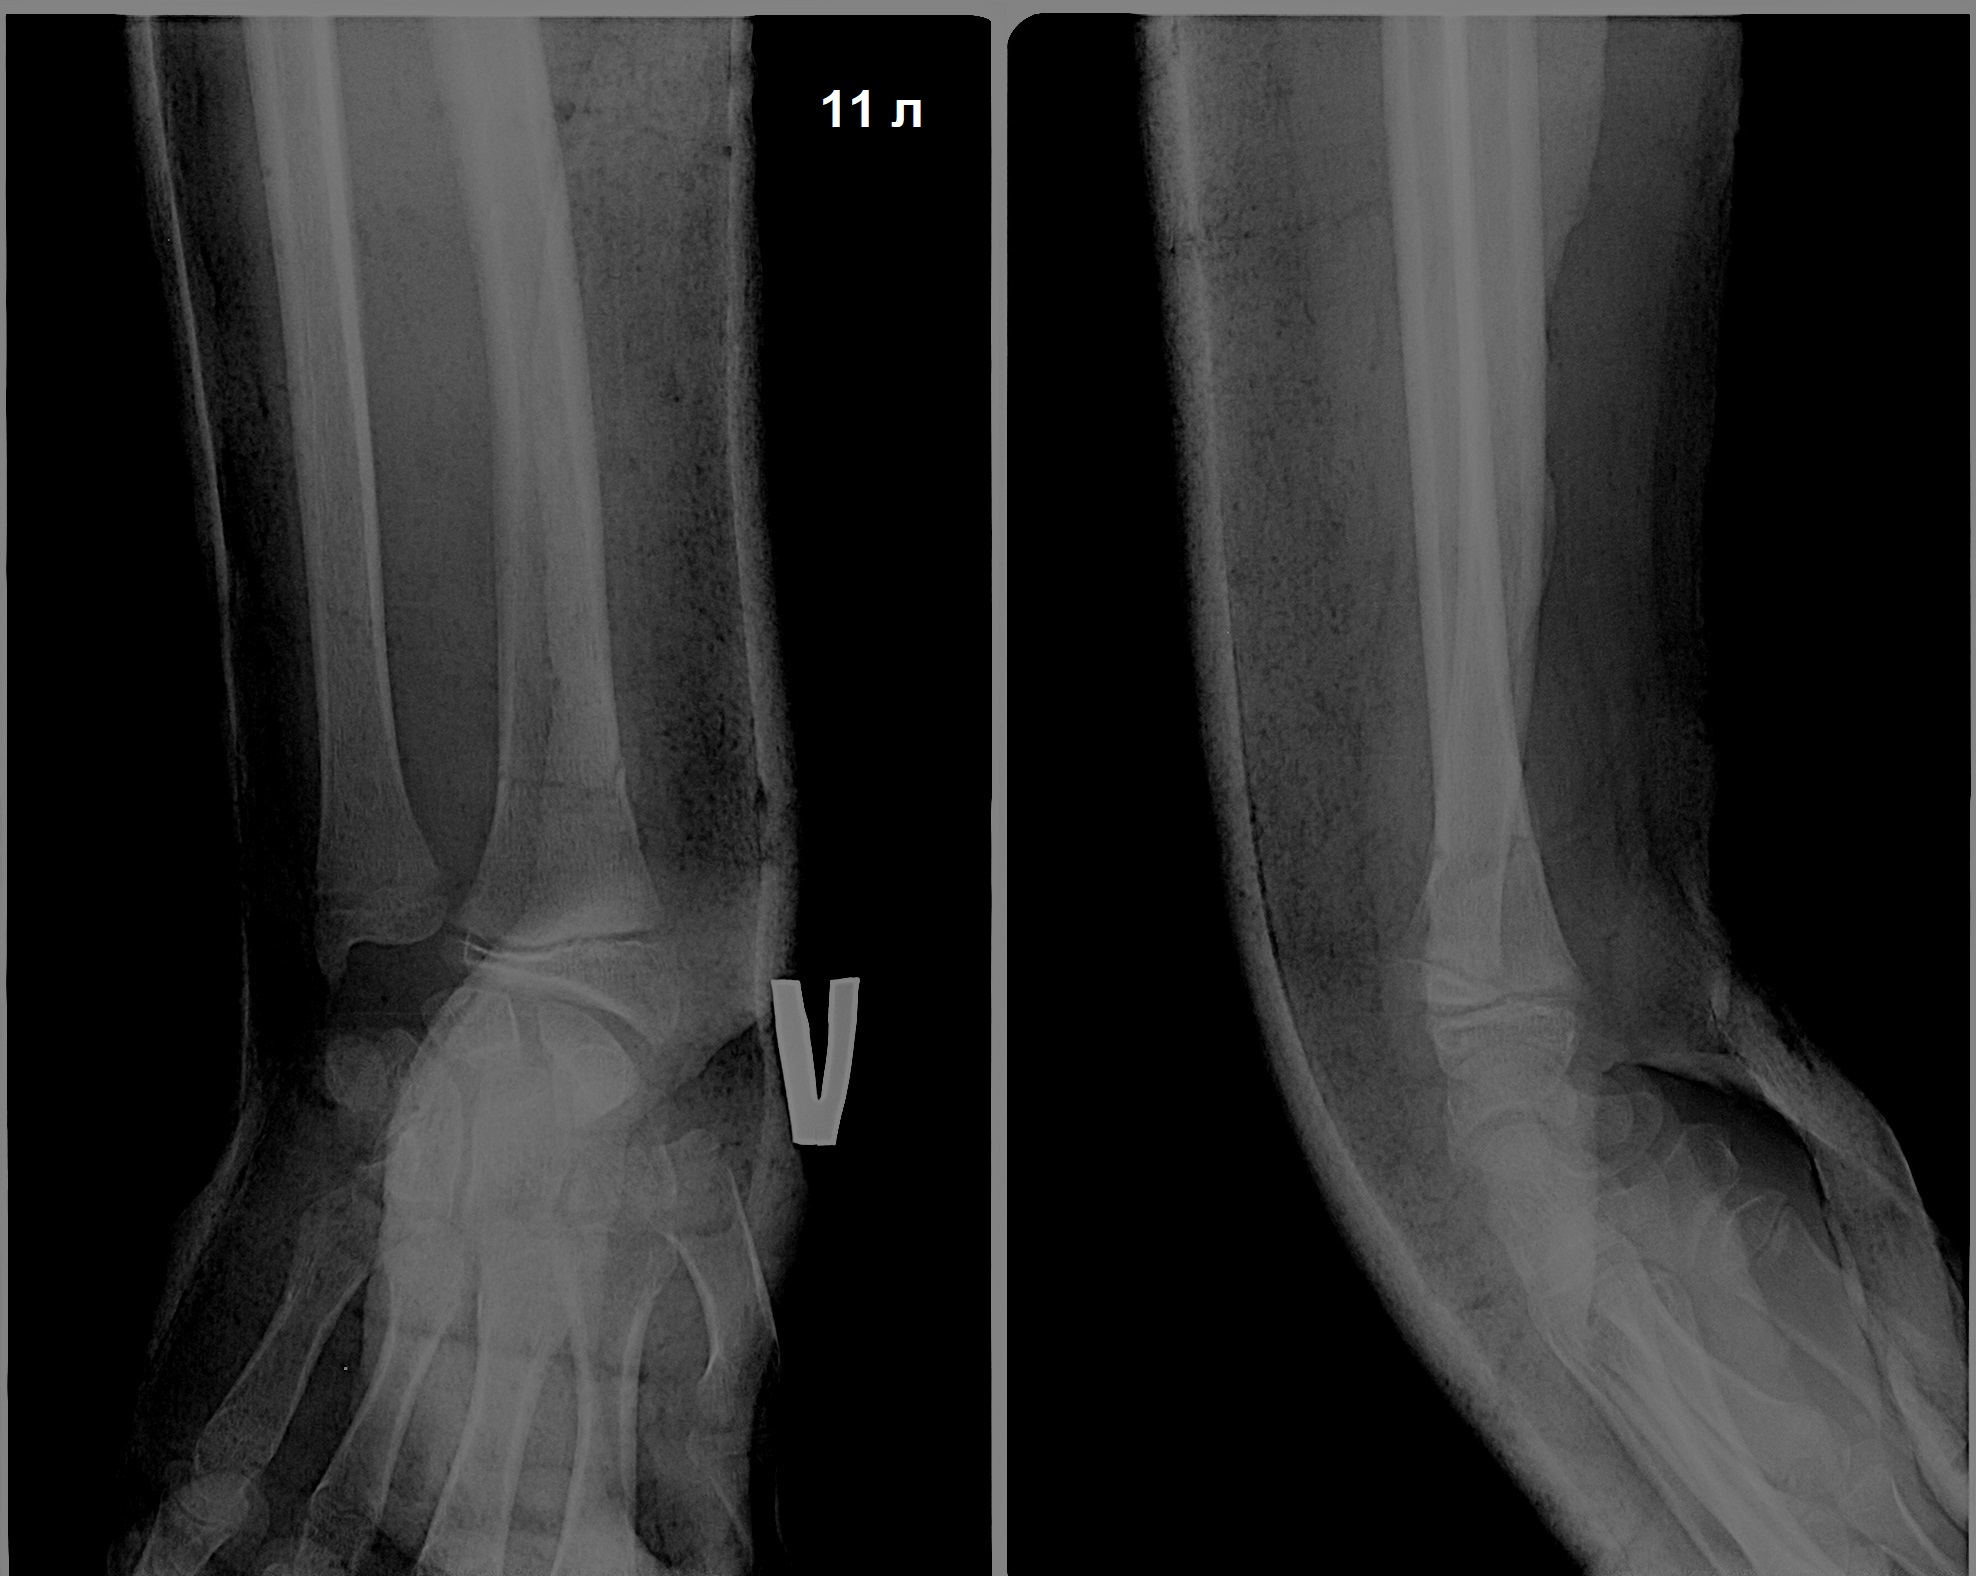

Давайте разберём алгоритм действий на конкретном примере. Девочка одиннадцати лет упала на руку и сломала её.

Ещё до рентгена понятно, что лучевая кость сломана в нижней трети и отломок смещен "к тылу", то есть это перелом Коллеса. Смотрим рентген.

Выясняется, что сломан ещё и шиловидный отросток локтевой кости.

Плюсом к этому в нижней трети локтевой кости имеется образование, судя по всему, фиброзная киста.